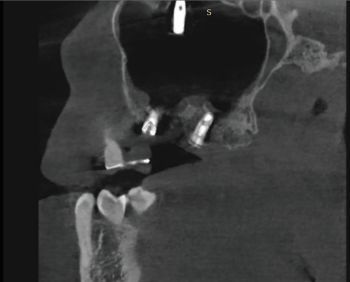

X-rays exams (i.e. OPG and CBCT) revealed the position of the displaced implant, which subsequently migrated near the ostiomeatal complex (OMC). It’s worth pointing out that immediately after their displacement, dental implants are usually located on the floor of the maxillary sinus or in the immediate vicinity; after a while, the displaced implants start to migrate against the gravitational force in the direction of the maxillary sinus ostium (as reported in the present clinical case) thanks to the strong mucociliary clearance by the sinus mucosa as well as nasal and intrasinus pressure changes. Notably, no reactive changes of the sinus membrane were observed (Figs. 1–5).

Fig. 3: Pre-op CBCT radiographic exam (panorex)